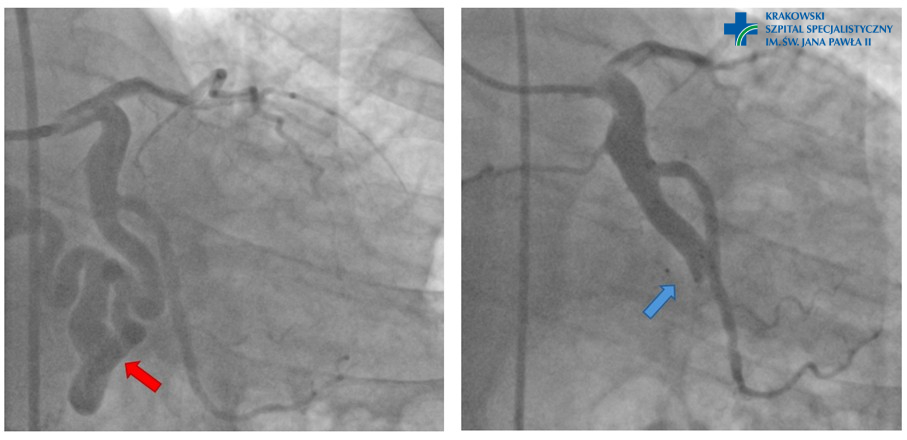

Po lewej stornie ryciny oznaczono czerwoną strzałką dużą przetokę naczyniową pomiędzy gałęzią okalającą lewej tętnicy wieńcowej a żyłą główną górną. Na lewej ryciny oznaczono niebieską strzałką miejsce zamknięcia przetoki za pomocą urządzenia do zamykania ubytków serc (widoczne dwa czarne markery).

W ostatnim czasie w naszym szpitalu lek. med. Maciej Panek z Oddziału Klinicznego Choroby Wieńcowej i Niewydolności Serca z Pododdziałem Intensywnego Nadzoru Kardiologicznego przeprowadził wraz z zespołem zabieg zamknięcia dużej, wrodzonej przetoki naczyniowej pomiędzy gałęzią okalającą lewej tętnicy wieńcowej a żyłą główną górną – u młodego, 48-letniego pacjenta. Procedura wykonana była z dostępu przez prawą tętnicę udową wspólną – z uwagi na rozmiary i stopień krętości naczynia, pierwsza próba wykonania zabiegu przez tętnice promieniową była nieskuteczna. Do początkowego odcinka przetoki naczyniowej wprowadzono specjalne urządzenie zamykające przetokę, oszczędzając przy tym samą gałąź okalającą lewą tętnicę.